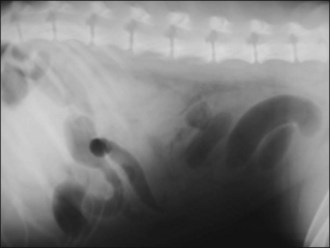

Acute GDV can usually be diagnosed on the basis of history, signalment and physical examination; radiography is generally not required. However, radiography may allow differentiation of gastric dilatation alone from gastric dilatation with volvulus. Radiography should not be performed until after fluid therapy and analgesia have been commenced and only if the patient is compliant as is usually the case. Radiography may be performed during the initial fluid resuscitation but should not delay gastric decompression. A single radiograph with the patient in right lateral recumbency is all that is typically required. Examples of radiographic findings are shown in Figures 29.3-29.6.

Figure 29.4 Right lateral abdominal radiograph showing gastric dilatation with volvulus with the Popeye arm (double bubble, reverse C) configuration.

Figure 29.5 Right lateral abdominal radiograph showing gastric dilatation with volvulus; compartmentalization by a soft tissue fold is present. Gas-filled intestines are often identified as in this example.